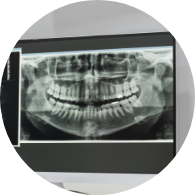

자료 채득

X-ray, 구강 내ㆍ외 카메라 사진, 치아 모형, 턱관절 및 치주 상태, 전신 질환 유무, 가족력 검사 등을 ​​​​​​​통해 진단 자료 수집